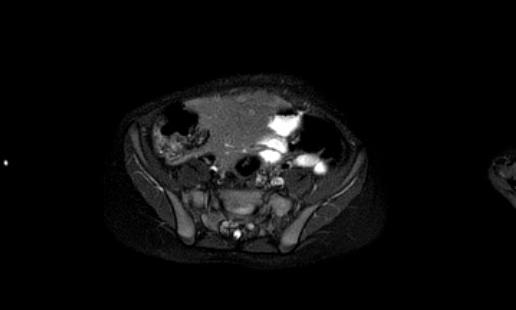

Hình ảnh trục T2 weighted cho thấy các phần có tín hiệu cao của khối u, có thể là mỡ hoặc dịch.

Hình ảnh T1W tăng cường tương phản có ức chế mỡ.

Các vùng tín hiệu cao bị ức chế, điều này cho thấy đó là mỡ.

Lưu ý

mối liên quan chặt chẽ với động mạch mạc treo tràng trên, có thể bị tổn thương

trong quá trình phẫu thuật.